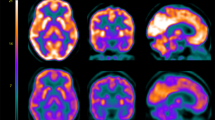

Mean distribution of BGU, MOR availability and CB1R availability are shown in Fig. 1. Descriptive Pearson correlations of the sample are presented in the Supplementary Fig. 1 and Supplementary Table 2.

Top: Mean brain glucose uptake (BGU) of the 38 [18F]FDG scans (19 low-risk and 19 high-risk subjects). Middle: Mean binding potential (BPND) of the 41 [11C]carfentanil scans (22 low-risk and 19 high-risk subjects). Bottom: Mean volume of distribution (VT) of the 36 [18F]FMPEP-d2 scans (20 low-risk and 16 high-risk subjects).